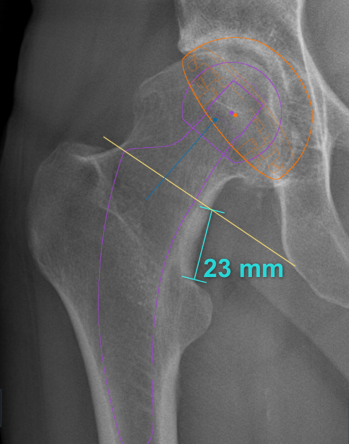

- Bone economy and the femoral neck: With this stem format, the femoral neck cut is situated at an average of 15 - 25 mm above the lesser trochanter. Moreover, it is the sparing of this segment of the femoral neck that will guide the implant and therefore mean that femoral parameters such as length and offset will be restored. We will return to this theme.

Neck-shaft angle

The “round the corner” technique of stem implantation involves following the medial femoral cortex, meaning that the physiological medial curvature of each patient can be restored. The main condition is to retain sufficient femoral neck to guide the insertion path of the compactors preparing the way for the stem. This means it is important to uphold the principle of not cutting the femoral neck too extensively, above all in coxa vara hips. The cut is therefore often made higher than it would be for a standard stem, usually between 15 and 25 mm above the lesser trochanter. It is essential to plan the surgical intervention thoroughly in order to obtain the desired result. With this type of stem and by following this technical principle, the prosthetic hip is restored to a neck-shaft angle that is similar to that of the native hip.

Planning - The intervention begins before the incision, with the preparation. As Franklin said “If you fail to plan, you are planning to fail”. Pre-operative planning is an integral part of the success of the operation, in that it involves assessing the native hip parameters (which should be restored) and anticipating any peri-operative difficulties. This planning means that the precise size of the final stem can be determined, ensuring optimal intramedullary filling, and the correct height of the femoral neck cut can be identified. Under-sizing risks secondary subsidence, especially in somewhat valgus tilted femurs . Stem positioning must follow the calcar rather than the diaphyseal axis, which will enable the femoral offset to be restored. Restoring an optimal overall offset also depends on the depth to which the socket is burred, as this may sometimes need to be compensated for on the femoral side. Finally, it is important to take femoral torsion into account. All this points to the value of 3-dimensional planning systems that take these parameters into account (EOS or CT scan), and are more complete than the conventional practice of sketching on AP radiographs.

Femoral neck cut -The femoral neck cut is made higher than for a straight stem since the stem will rest on the remaining neck segment to find its orientation. The optimal height and orientation are determined in the planning. Peri-operative fluoroscopy is relatively straightforward to carry out in the anterior approach in dorsal decubitus, and may be useful for a surgeon’s first few interventions, since there is always a tendency to cut too vertically and therefore too low, reducing support of the calcar. The femoral neck cut should be made even higher if the patient has a coxa vara morphotype.